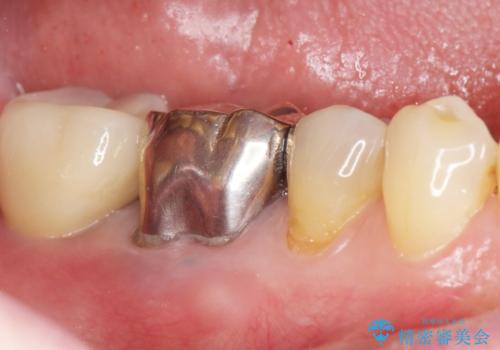

自然な見た目と咬み心地にご満足頂けました。

他院では難しいと言われていたインプラント治療が可能になり、喜んで下さいました。

インプラントの種類:スプライン ツイスト (HAコーティング)

固定様式:セメント固定

クラウンの種類:オールセラミッククラウン スタンダード